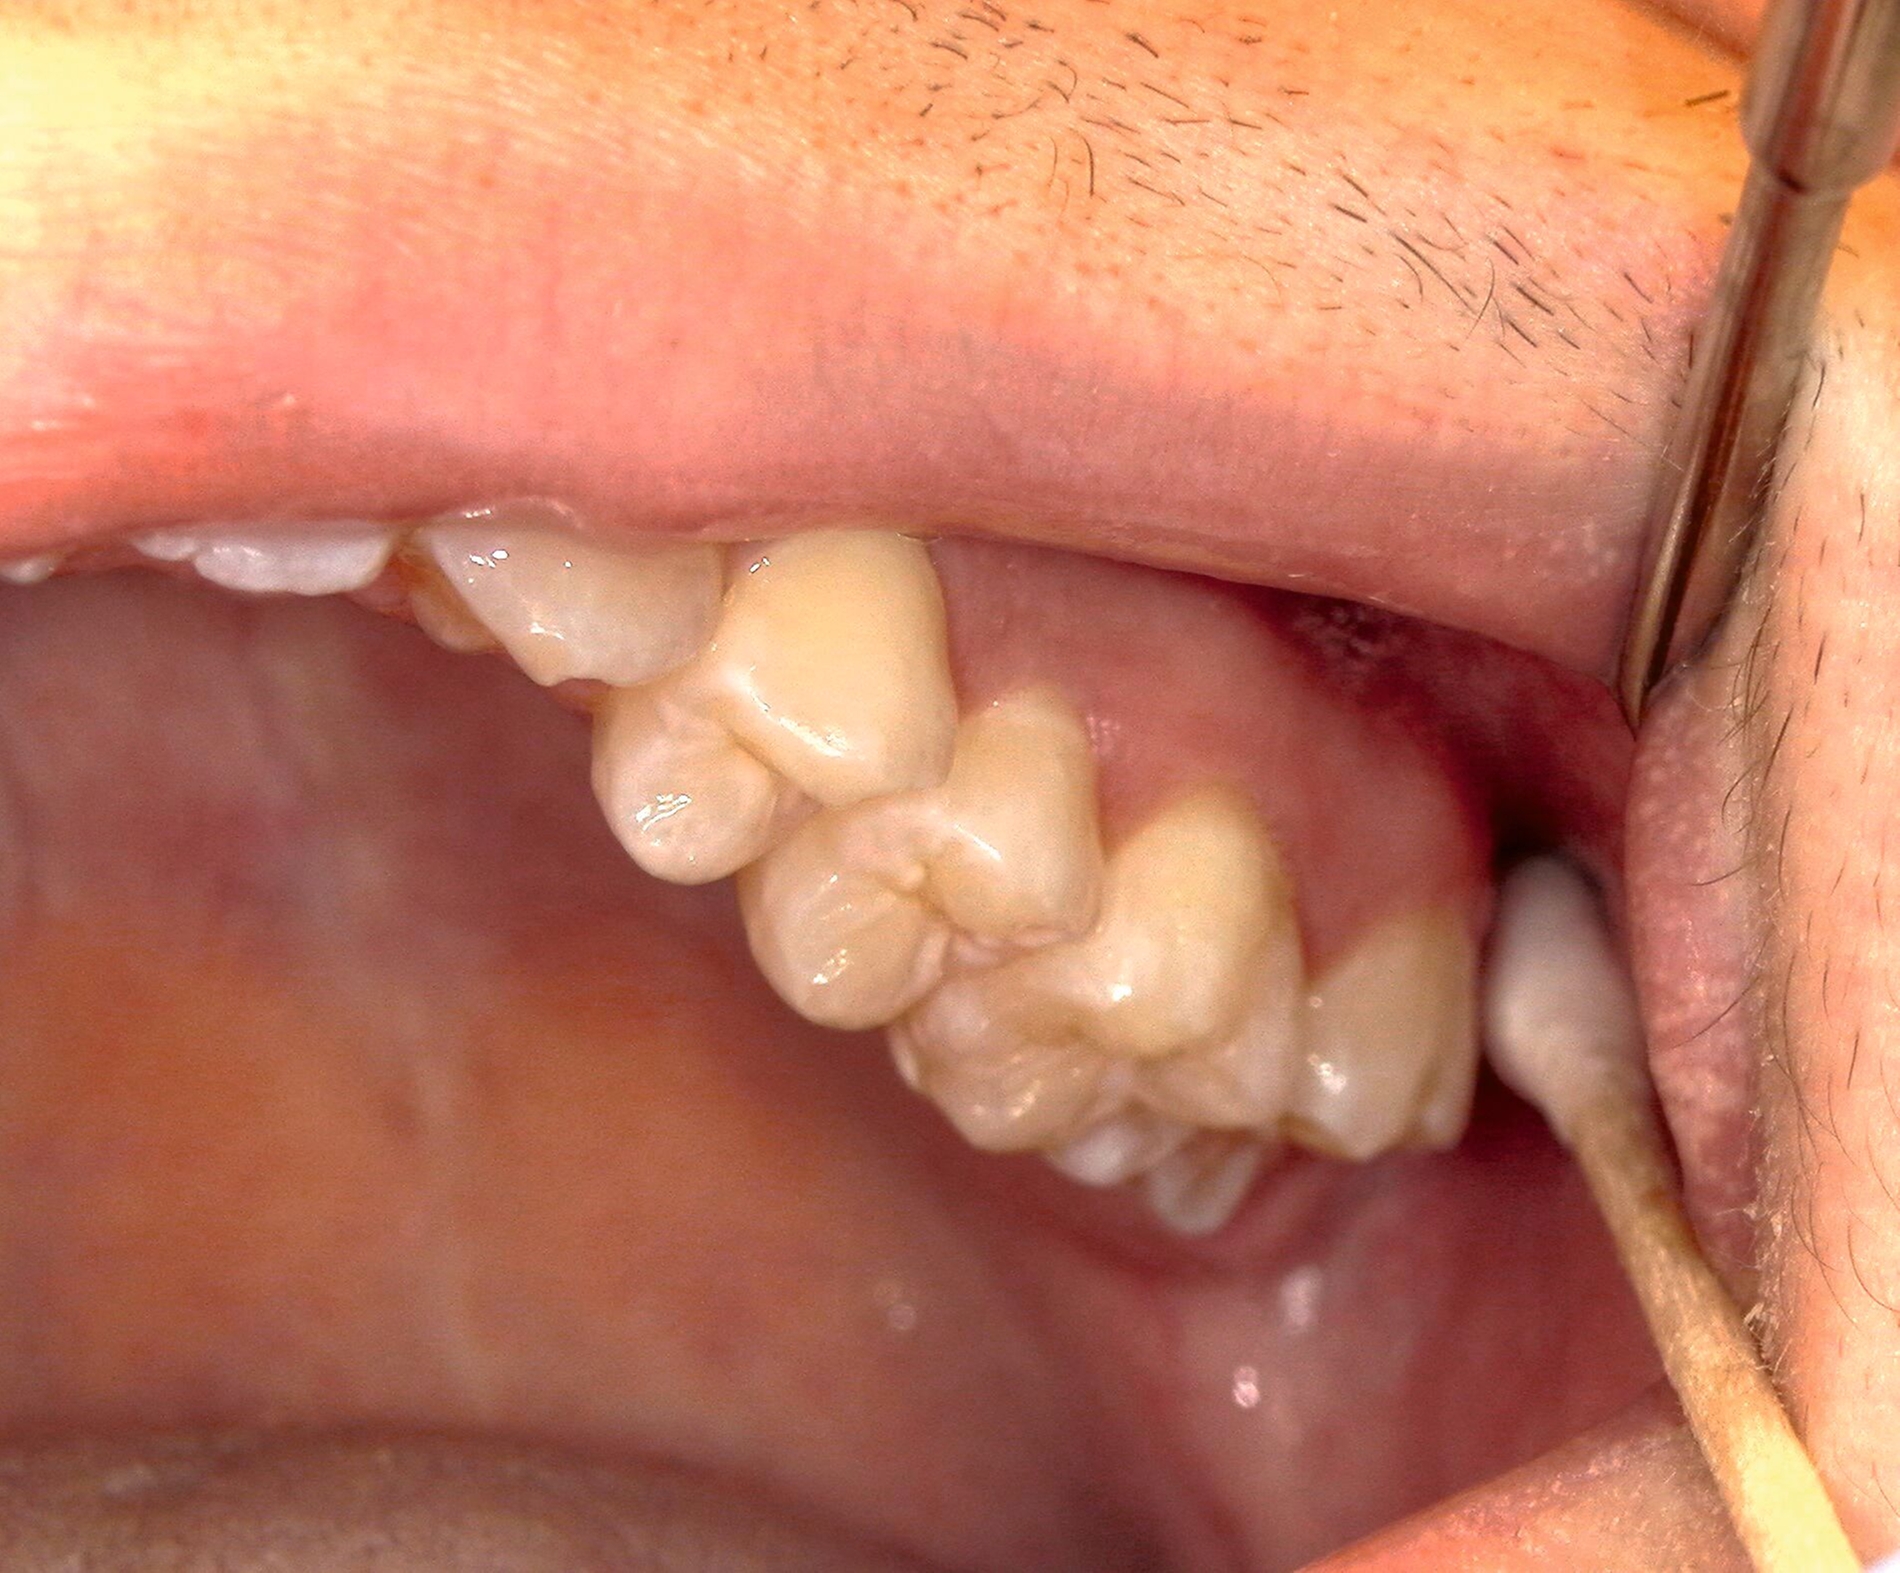

Allgemein kann eine präemptive Analgesie in Form einer präoperativen Gabe von 400-600 mg Ibuprofen eine Stunde vor dem Eingriff verabreicht werden, was sich positiv auf das Schmerzempfinden und den Bedarf postoperativ auswirken kann [Gutwald et al., 2019]. Zu Beginn des Eingriffs kann eine Lokalanästhesie durchgeführt werden. Bei dieser kommen entweder eine Oberflächenanästhesie, eine Infiltrationsanästhesie, eine Leitungsanästhesie (N. alveolaris inferior im Unterkiefer, N. palatinus major im Oberkiefer) oder eine intraligamentäre Anästhesie zum Einsatz (Abbildung 6) [Daubländer et al., 2016].

Zur Entfernung der unteren Weisheitszähne wird im Unterkiefer zunächst der aufsteigende Ast im Bereich der Linea obliqua palpiert. Verwendet man eine Pinzette zur Markierung (Abbildung 7), erfolgt die Schnittführung von dieser im senkrechten Winkel zum Knochen distal auf den zweiten Molaren zu, weiter im PA-Spalt bis mesial des zweiten Molaren. Liegt der Zahn tief verlagert oder anguliert, sollte man zur besseren Übersicht einen größeren Entlastungsschnitt unter Schutz des N. mentalis wählen.